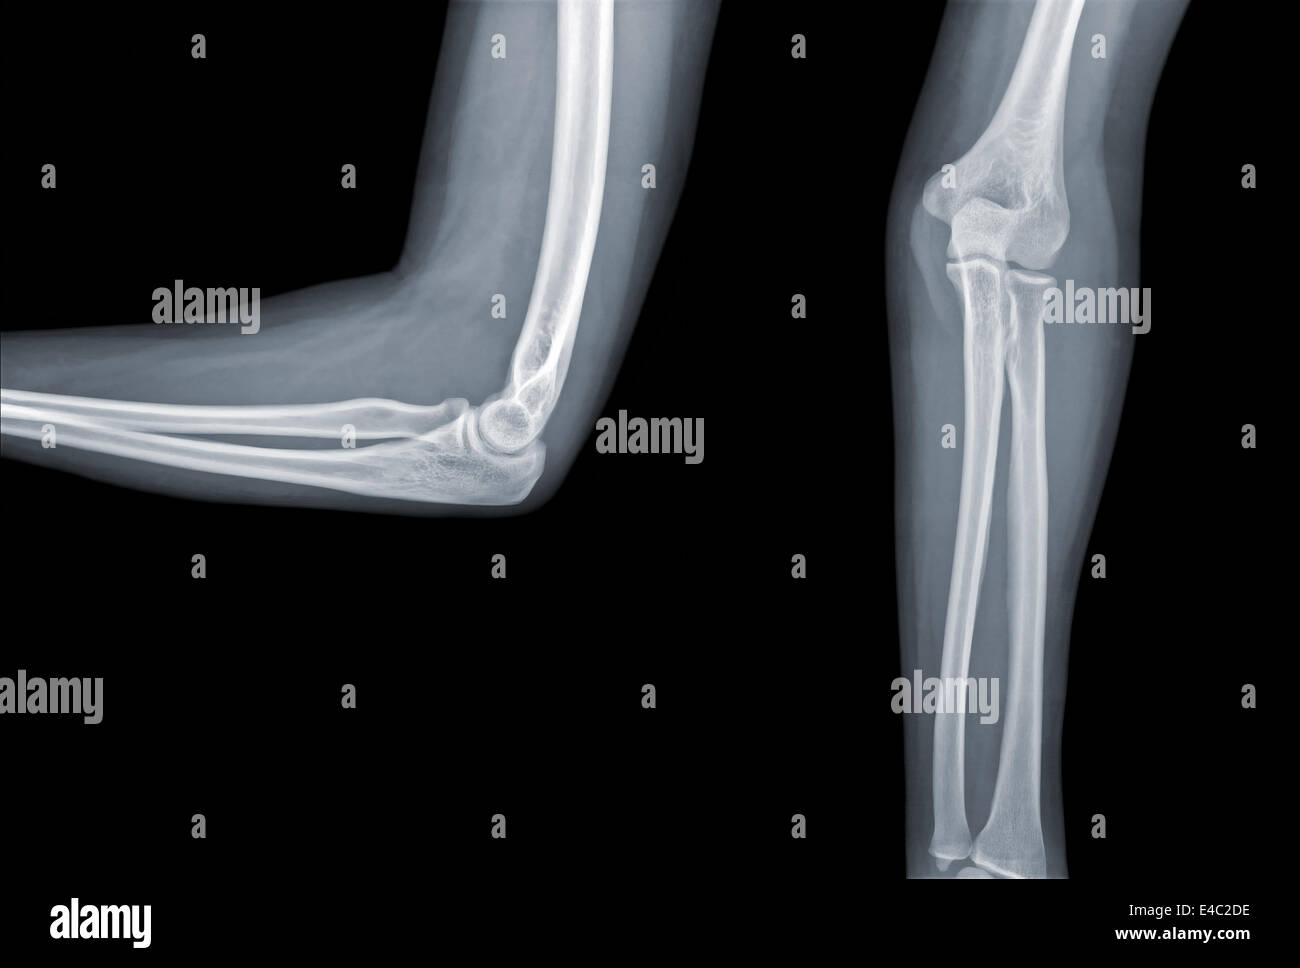

From www.researchgate.net

Anterioposterior (AP) and lateral Xrays of injured elbow. Download Elbow Injury X Ray The anterior fat pad is normally seen as a faint line running with the distal humerus, whilst the posterior fat pad is not seen in normal radiographs. Elevation of these fat pads,. What is the most common elbow fracture? Drawn down the anterior surface of. An elevated posterior fat pad is never normal, and a fracture or ligamentous injury must. Elbow Injury X Ray.